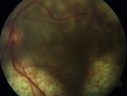

Ocular Lymphoma - Initially presented like auto-immune retinopathy280 views43 year old man: initial presentation - The vision in the left eye is blurry and opaque for about 2 weeks. In the central of the vision, when he covers the right eye, in the center of the left eye there is a film with a light in the middle. This has never happened before. He has not been sick for the last few months. A few weeks ago he saw waves on the floor when looking down but that has gone away. Since the vision loss started the vision has not changed much. The central vision is not getting better. Â

Labs normal. One positive antiretinal antibody - Arrestin

VA improved over 2 months to normal. Then the patient had 2 more episodes of self-limited vision loss (no treatment). Then 2 years later he presented with a diagnosis of CNS lymphoma and later developed subretinal deposits (last images)Oct 25, 2021